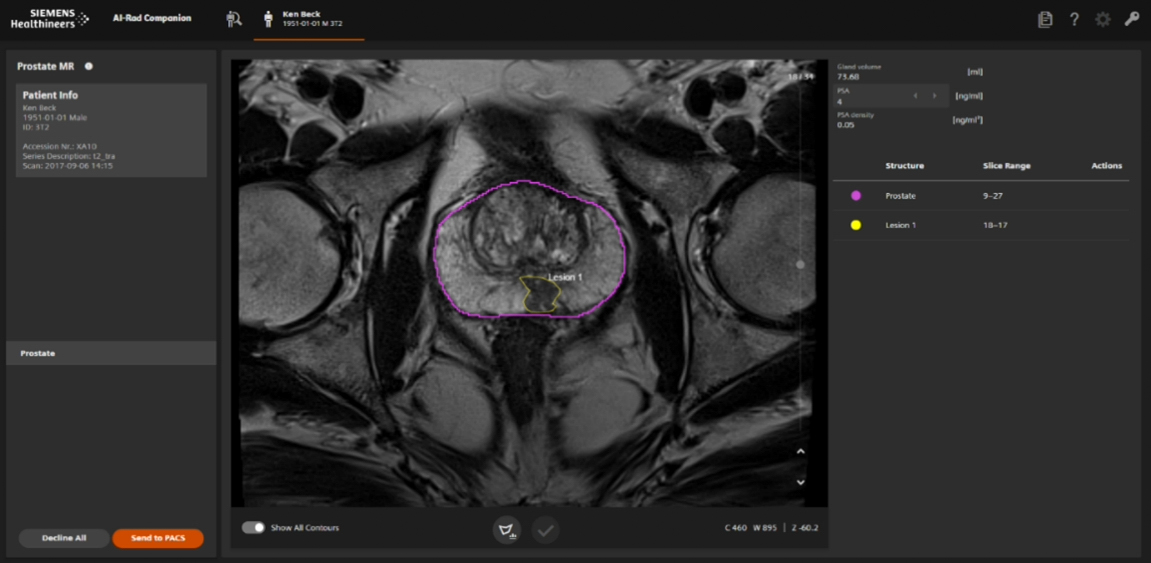

Uno de los principales clientes de Intel en el sector salud, Siemens Healthineers, es una empresa global de tecnología médica centrada en llevar innovación tanto a profesionales de la salud como a pacientes. En el evento Intel Vision, Siemens Healthineers presentó su software AI-Rad Companion, impulsado por procesadores Intel Xeon Scalable optimizados para IA en el edge.

AI-Rad Companion es un conjunto de algoritmos de inteligencia artificial que ayuda a los médicos a acelerar el diagnóstico y la planificación terapéutica. A partir de un escaneo por tomografía (CT) o resonancia magnética (MRI), el sistema segmenta instantáneamente las estructuras anatómicas y distingue las células cancerosas para que sean objetivo de radiación, preservando los tejidos sanos.

Mediante el uso de OpenVINO™, el toolkit de código abierto de Intel para acelerar inferencias de IA, AI-Rad Companion puede identificar órganos y datos anatómicos. Esto le permite reconocer incluso las anomalías más pequeñas y alertar al médico sobre su ubicación y naturaleza.

Este sistema puede asistir en diagnósticos de enfermedades en pulmones, cerebro, próstata y trastornos neurodegenerativos como el Alzheimer. Al acelerar la planificación del tratamiento, contribuye a reducir los costos médicos.

AI-Rad Companion ayuda a los médicos a identificar, medir, caracterizar y cuantificar anomalías, lo que reduce el tiempo de interpretación en casos complejos de imágenes médicas. Y gracias a la flexibilidad de los procesadores Xeon Scalable, los centros médicos pueden usar el software tanto en la nube como en servidores locales.